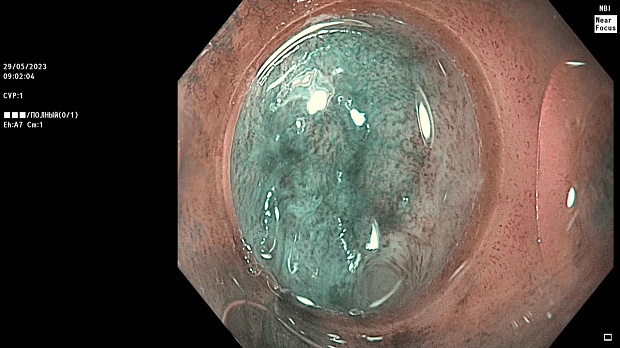

Иллюстрация №2: Эндофото. Сидероз нижней трети пищевода, осмотр в белом свете в близкофокусном режиме

Согласно полученным данным - в среднегрудном и нижнегрудном отделах пищевода определялась проксимальная граница плоских неправильной формы поверхностных рубцов суммарной протяженностью до 8,0 см. На этом фоне в зонах поверхностных рубцов по задней полуокружности визуализировались участки гиперпигментации в темный цвет (Рис. 1). При исследовании в режиме Dual Focus было отмечено наличие мелких (до 0,001 см) черно-коричневых включений, расположенных субэпителиально - в строме слизистой оболочки, сливания их в единый конгломерат не определялось (Рис. 2). При эндосонографии с применением минидатчика с частотой сканирования 20МГц выявлено, что все слои стенки четко дифференцируются, не утолщены, в слизистой оболочки визуализированы мелких гиперэхогенные включения с эхотенями (Рис. 3).

В пищеводе в шейном его отделе на уровне 16 см от резцов циркулярно визуализированы единичные синюшные флебоэктазии размерами до 0.5 см. Дистальнее пищевод визуально не изменен до уровня 28 см от резцов, где определяется проксимальная граница плоских неправильной формы поверхностных рубцов, распространяющихся до уровня 36 см от резцов. На этом фоне в зонах поверхностных рубцов по задней полуокружности визуализированы участки гиперпигментации в черно-коричнеый цвет. При осмотре в режиме Near Focus с увеличением - между зон пигментации определяются расширенные капилляры типа II по Inoue-классификации. При биопсии отмечена десквамация плоского эпителия, визуализированы мелкие черно-коричневые включения в строме слизистой оболочки, размеры их до 0,001 см, сливания их в единый конгломерат не отмечается. При эндосонографии с датчиком 20Мгц в исследуемой зоне в слизистой оболочке определяются гиперэхогенные включения, в то время как в подслизистом слое - зоны со сниженной эхогенностью. При биопсии отмечается уплотнение ткани, однако истинной фрагментации не определяется. Уровень Z-линии совпадает с уровнем анатомического кардиоэзофагеального перехода. Розетка кардии эластичная, смыкается не полностью, расположена на уровне пищеводного отверстия диафрагмы.